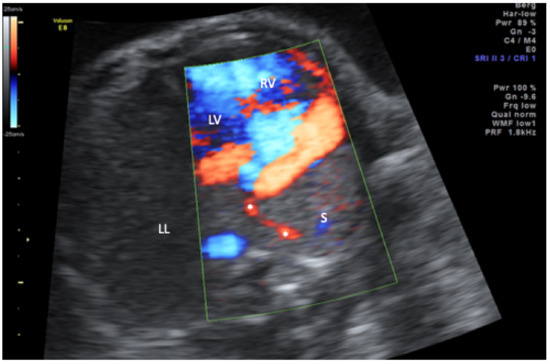

| 1 | 34 + 1 | mediastinal shift; dextroposition of the heart, right pulmonary hypoplasia, partial anomalous pulmonary drainage (scimitar vein) | 39 + 1 | Feeding vessel from coeliac trunk, secundum atrial septal defect | Coil occlusion of feeding vessel, pulmonary hemorrhage with respiratory deterioration, intracranial hemorrhage, diabetes insipidus centralis, exitus at 1 month |

| 2 | 38 + 0 | mediastinal shift; dextroposition of the heart, right pulmonary hypoplasia, partial, anomalous pulmonary drainage (scimitar vein), right sided diaphragmatic hernia; coarctation; duplication 10q22.1–10q23.2 | 39 + 2 | Feeding vessel from abdominal aorta, pulmonary hypertension | Coil occlusion of feeding vessel, intractable pulmonary hypertension, exitus at 6 months |

| 3 | 20 + 2 | mediastinal shift; dextroposition of the heart, right pulmonary hypoplasia, partial anomalous pulmonary drainage (scimitar vein) | 35 + 5 | Feeding vessel from abdominal aorta, hypoplastic aortic arch; secundum atrial septal defect; anomalous supracardiac pulmonary drainage of left pulmonary veins in brachiocephalic vein | Plug occlusion of feeding vessel, reinsertion of left pulmonary veins, patch reconstruction of aortic arch, postoperative hydrocephalus; hypoplastic corpus callosum; ventilation malfunction hypoxic crisis with bradyasystole, exitus at 6 months, |

| 4 | 31 + 1 | mediastinal shift; dextroposition of the heart, right pulmonary hypoplasia, anal atresia, diaphragmatic hernia, hemivertebrae, single umbilical artery, renal dysplasia | 33 + 6 | partial anomalous pulmonary drainage (scimitar vein), Feeding vessels from thoracic aorta, hypoplastic aortic arch, secundum atrial septal defect, VACTERL association | Plug occlusion of feeding vessel and 2 MAPCAs in neonatal period, multiple bronchial stent placements, 4 years old |

| 5 | 22 + 2 | mediastinal shift; dextroposition of the heart, right pulmonary hypoplasia, partial anomalous pulmonary drainage (scimitar vein) | 31 + 0 | Feeding vessel from coeliac trunk, secundum atrial septal defect, mild coarctation | Plug occlusion of feeding vessels in neonatal period, thriving with mild pulmonary hypertension, 7 years old |

| 6 | 17 + 2 | mediastinal shift; dextroposition of the heart, right pulmonary hypoplasia, partial anomalous pulmonary drainage (scimitar vein), single umbilical artery, left persistent superior caval vein | 40 + 0 | 2 Feeding vessels from thoracic aorta, anomalous drainage of right sided pulmonary veins in left atrium, secundum atrial septal defect | Plug occlusion of feeding vessels in neonatal period and at age of one year. Correction of right pulmonary veinous drainage with intra-atrial tunnel and ligation of persisting ductus arteriosus at age of 2 years, infantile cerebral palsy; tracheostoma; Percutaneous endoscopic gastrostomy(PEG) placement, 10 years old |